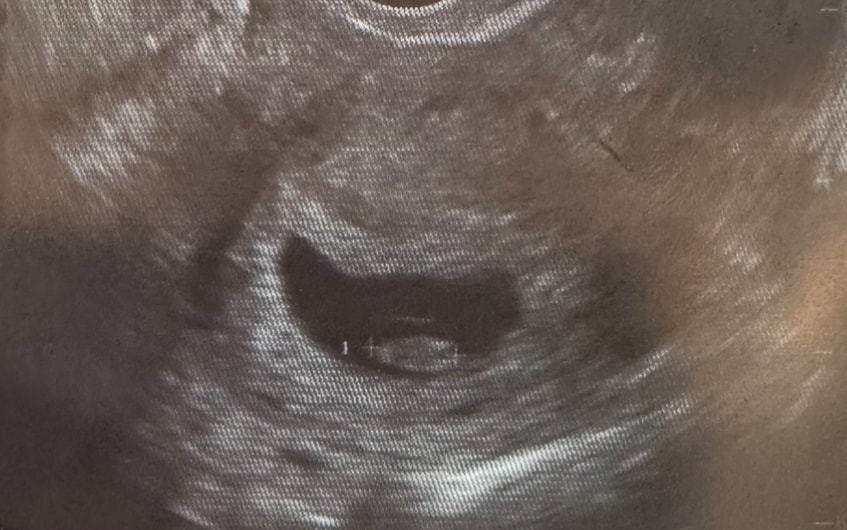

Была на узи, результаты прилагаю. По моим подсчётам 7 недель и 4 дня. Смущает расположение малыша и его строение, узист говорила что есть зачатки ручек, ножек, но форма больше напоминает гусеницу, это нормально? И нормальный ли ктр при таком сроке

Сердечко 164 уд.

Вот мой в 7 недель 2 дня, с КТР 10.7. Просто капля😂 Все у вас отлично, подождите недельку-две, уже будет шарик с ножками и ручками. ЧСС у вас нормальный, не низкий и не высокий, все как надо